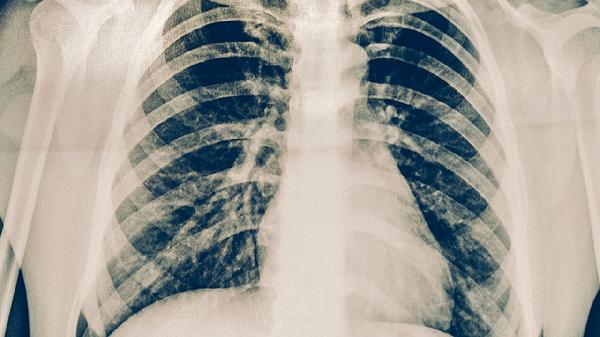

2、影像学特征

肺结核胸部CT常显示上肺野斑片影、树芽征或空洞形成,病灶多呈多态性改变。肿瘤影像学表现为孤立性肿块或结节,边缘可见分叶、毛刺征,增强扫描呈不均匀强化。纵隔淋巴结结核多为环形强化,肿瘤转移淋巴结常为实性肿大。